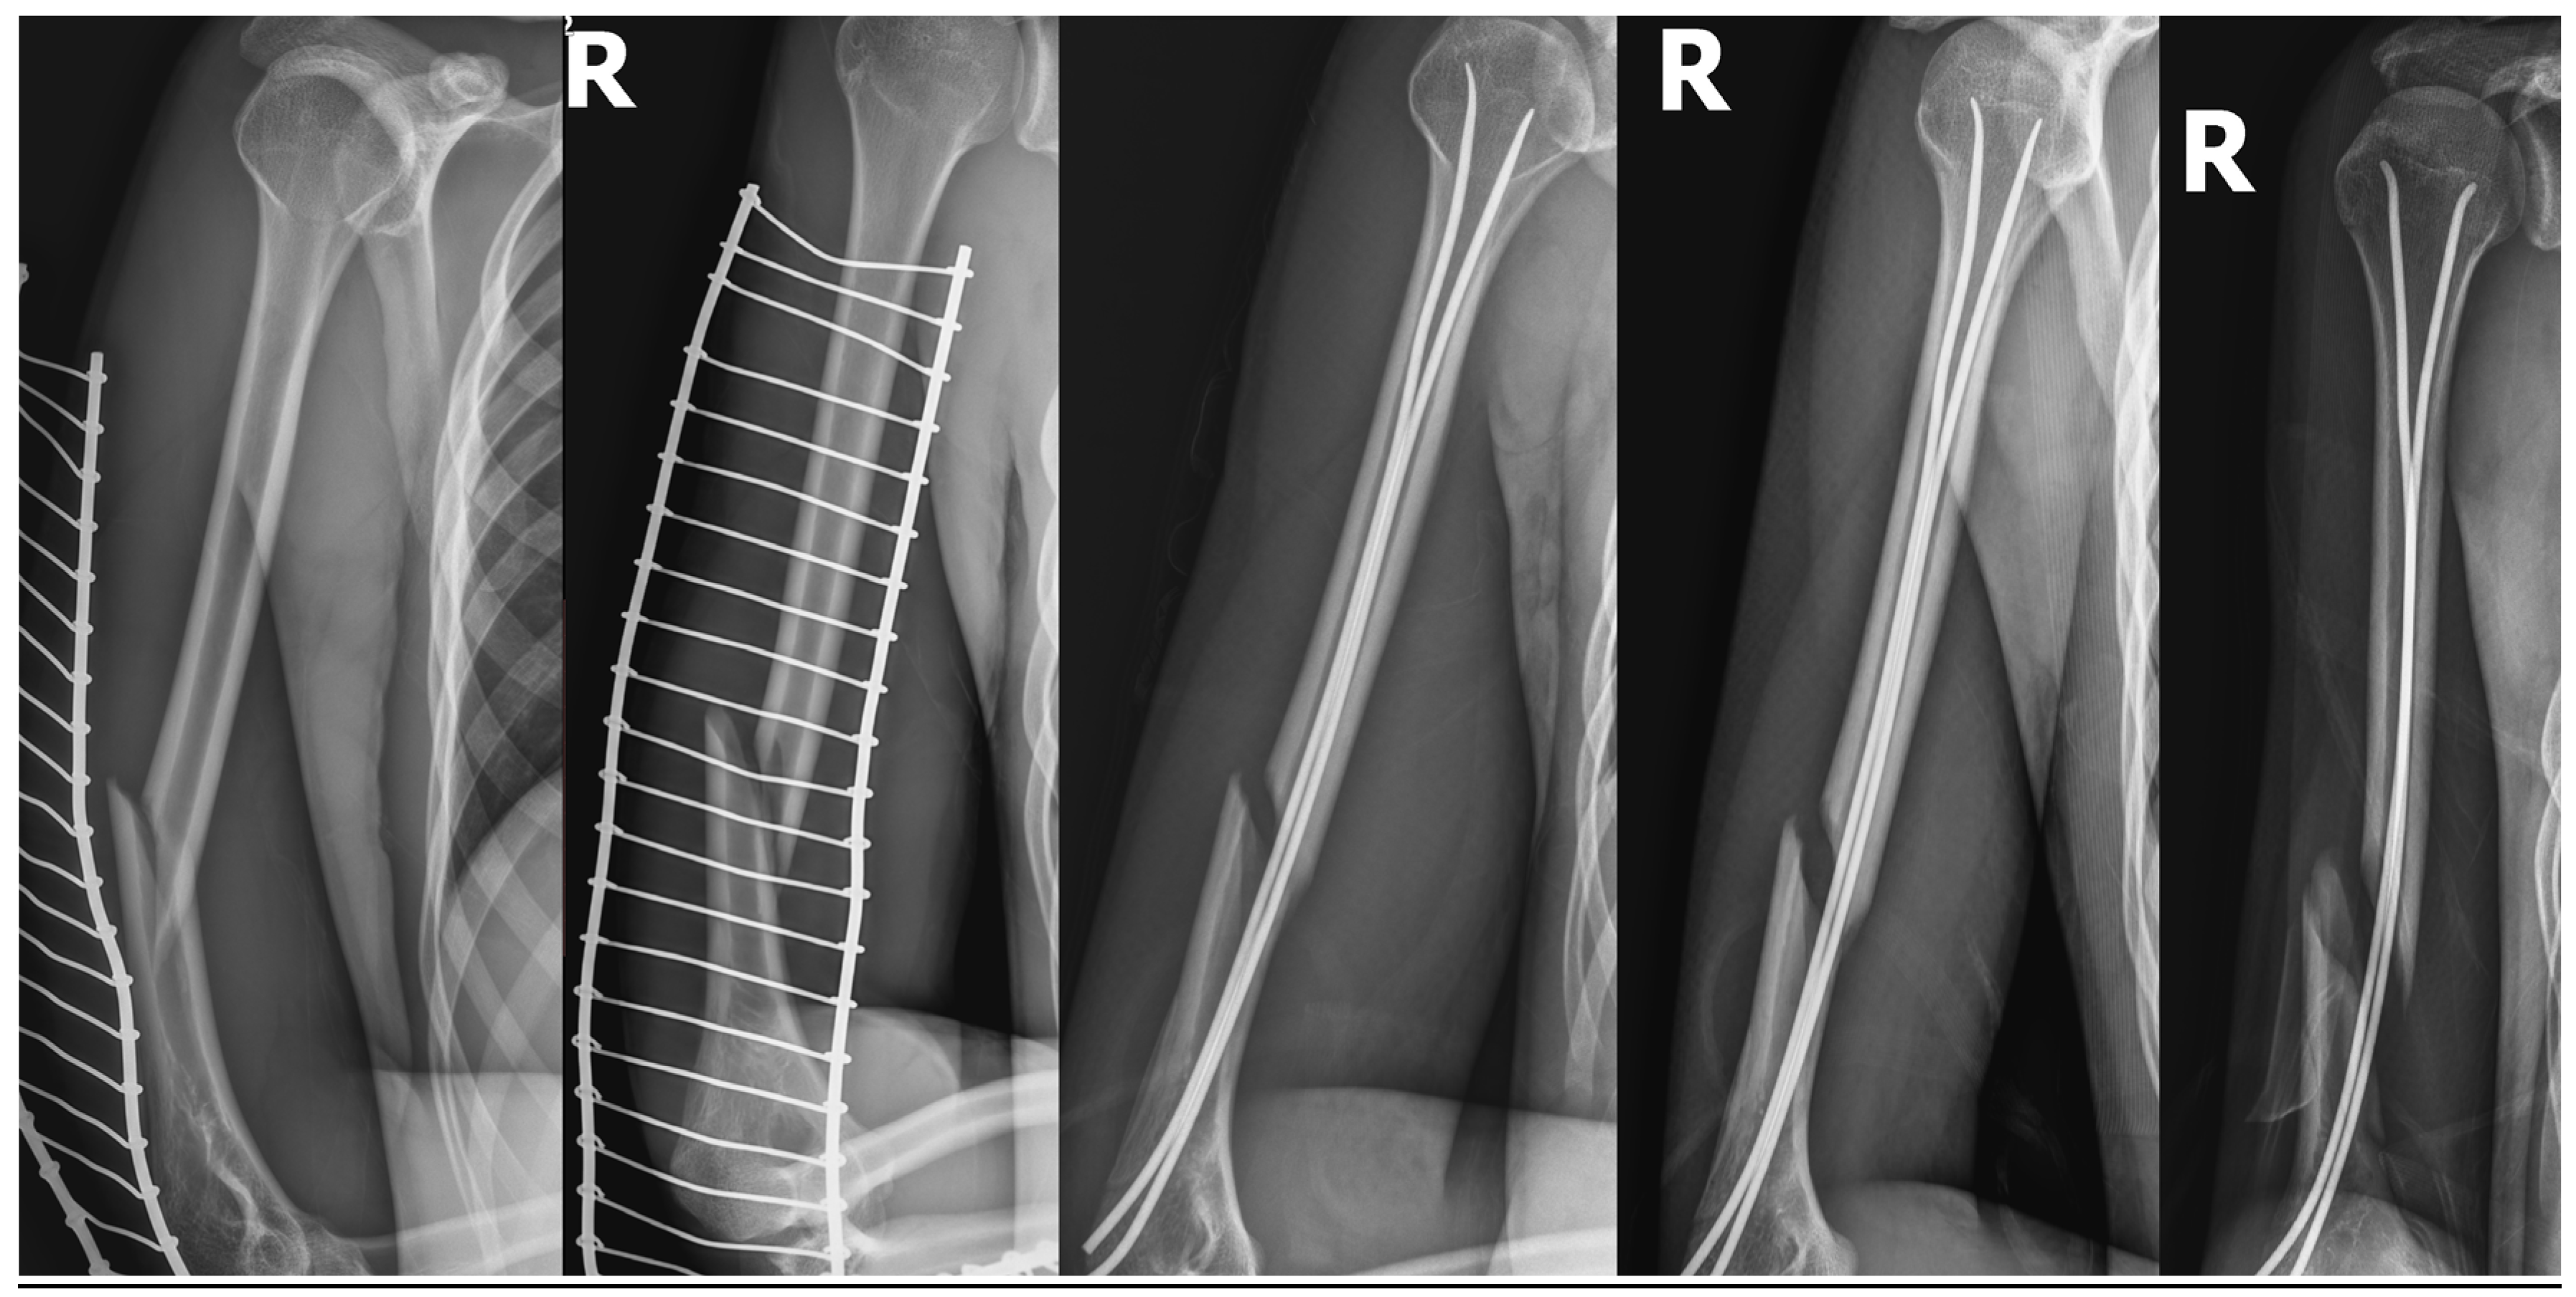

Adult Forearm Fractures OrthoInfo AAOS Radial Arm Fracture Treatment A distal radius fracture is a break in the part of the forearm bone closest to your wrist. Learn about the causes, symptoms, diagnosis and treatment of distal radius fractures, the most common type of forearm fracture. What is the treatment for a distal radius fracture? Treatment can be nonoperative or operative depending on fracture stability and fracture displacement as. Radial Arm Fracture Treatment.

A fresh look at radial shaft fracture fixation The lateral approach to Radial Arm Fracture Treatment A distal radius fracture is a break in the part of the forearm bone closest to your wrist. This clinical practice guideline is based on a systematic review of published studies on the treatment of distal radius. Fracture displacement (whether the broken bones shifted) comminution (whether there are Forearm fractures can involve the radius or the ulna, or both bones,. Radial Arm Fracture Treatment.

radial fracture Image Radial Arm Fracture Treatment Forearm fractures can involve the radius or the ulna, or both bones, and can result from falls, direct impact or landing on an outstretched arm. Learn about the different types of forearm. This clinical practice guideline is based on a systematic review of published studies on the treatment of distal radius. Treatment can be nonoperative or operative depending on fracture. Radial Arm Fracture Treatment.

Short arm cast is as effective as long arm cast in maintaining distal Radial Arm Fracture Treatment What is the treatment for a distal radius fracture? This clinical practice guideline is based on a systematic review of published studies on the treatment of distal radius. Learn about the causes, symptoms, diagnosis and treatment of distal radius fractures, the most common type of forearm fracture. Forearm fractures can involve the radius or the ulna, or both bones, and. Radial Arm Fracture Treatment.